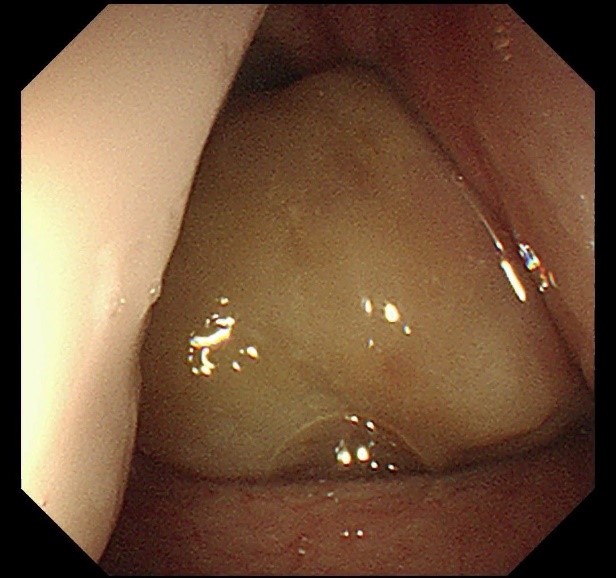

手术室内,气氛紧张而凝重。当支气管镜顺利进入,眼前的景象令人揪心:声门处管腔狭窄程度高达95%,巨大的白色肿物如同巨石般堵塞其中,表面光滑却质地坚硬。医疗团队沉着应对,先予圈套器多次圈套电切治疗,同时进行活检,样本送检常规病理。在精细操作下,声门得以部分暴露。在李健主任带领下的麻醉团队支持配合下,气管插管辅助通气。后续耳鼻喉科宋升桥主任凭借其深厚的专业功底,在支撑喉内镜下行喉部肿瘤等离子切除术。每一次操作都精准无误,每一个步骤都紧密衔接。在团队的共同努力下,肿物被逐步、分段切除,声带及喉室得以充分暴露,术后喉空间完全开放,管腔恢复通畅,如同被疏通的河道,重新恢复了生机,同时,凭借团队精湛的医术与充分完善的术前准备,避免气管切开带来的痛苦。术中患者生命体征始终保持稳定,术后患者呼吸明显顺畅,当晚便酣然入睡,目前患者正在住院恢复当中。